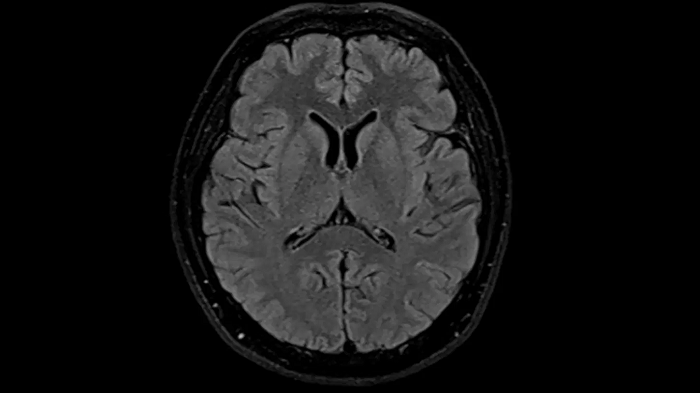

T2 TSE Dark Fluid with Deep Resolve

To produce high-resolution images, Deep Resolve, the Al-powered image reconstruction technology gets benefits from intelligent denoising and neural networks.

Deep Resolve Gain & Sharp

0.4 x 0.4 x 5.0 mm2

TA 4:32 min

MAC-ID: 7aaaa0195. Image Credit: Siemens Healthineers